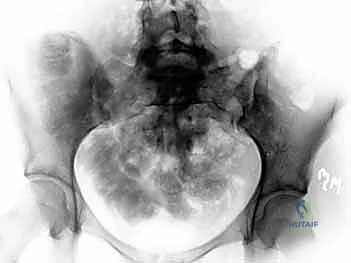

2. الأشعة السينية (X-rays): توفر نظرة أولية سريعة على كسور الحوض (AP, Inlet, and Outlet views).

3. التصوير المقطعي المحوسب (CT Scan): وهو المعيار الذهبي (Gold Standard) لتشخيص كسور الحوض والعجز. يقوم الدكتور هطيف باستخدام تقنية إعادة البناء ثلاثي الأبعاد (3D Reconstruction) لفهم هندسة الكسر بدقة متناهية قبل الدخول إلى غرفة العمليات.